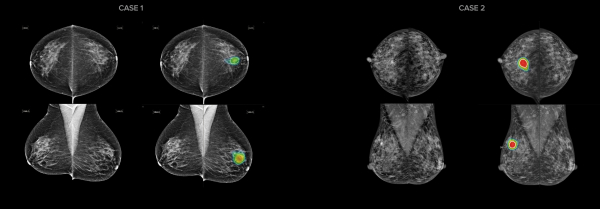

또한 병원은 유방암을 96% 정확도로 검출해 의료진의 진단을 보조하는 AI 영상판독시스템인 ‘루닛 인사이트 MMG’도 함께 도입했다. 영상의학과 의사는 루닛 AI 결과를 참고해 정상 케이스를 빠르게 선별하고, 비정상 케이스의 판독에 집중할 수 있다.

그리고 치밀한 유방조직 내의 작은 석회화 병변까지 발견하는 고해상도 이미지를 제공하며, 기존의 2D 유방촬영 장비에 비해 더욱 정교한 영상으로 작은 유방암도 정확하게 진단할 수 있다.